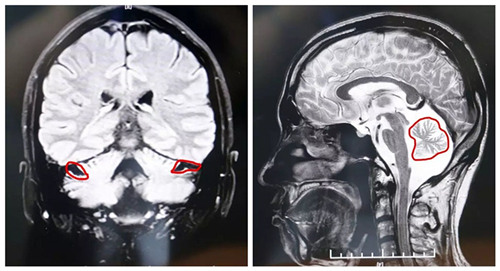

▲MRI顯示,患者小腦萎縮狀況明顯